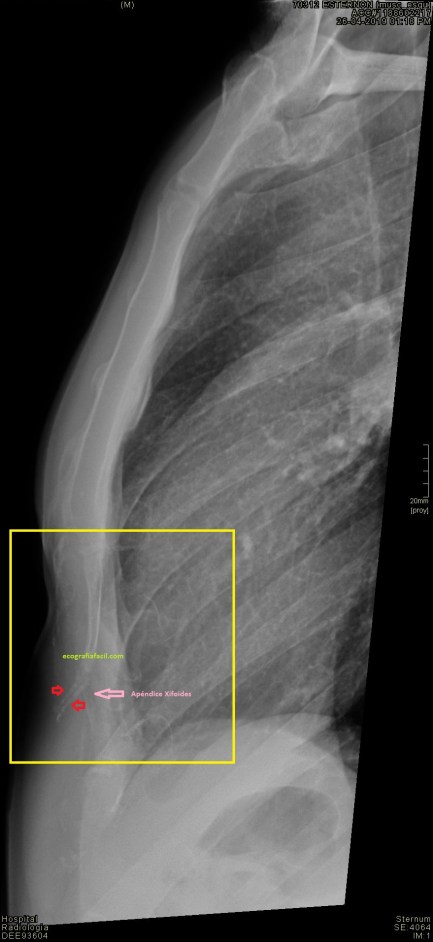

Es habitual, bastante más de lo que parece, pacientes que se tocan un bulto en línea media justo donde termina el esternón, a la altura de la Apéndice Xifoides y acuden a su médico por este motivo. A la palpación el médico corrobora dicho hallazgo y para descartar patología a dicho nivel pide ecografía de partes blandas para descartar cualquier tipo de neoformación.

Cuando el/la paciente llega a la sala exploramos la zona de interés y solemos encontrar que el apéndice xifoides está posicionado hacia anterior como vemos en la imagen 1. Lo ideal es realizar localización en corte axial para poder descartar una apéndice bífido, es una anatomía variable, en este caso te presento un apéndice cuya disposición es bífida, puedes repasar aquí los diferente tipos que podemos encontrar.